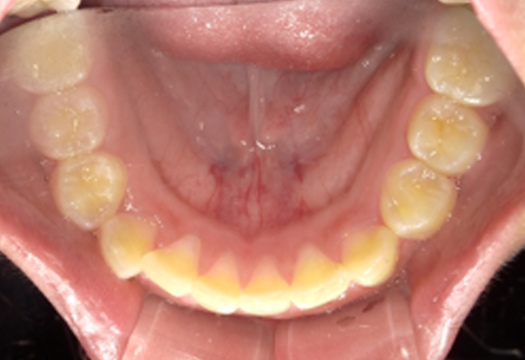

| Before | After |

|---|---|

![]() |

| 患者様の主訴 | 前歯が出ていてガタガタが気になるので矯正したい |

| 治療名 | 固定式拡大装置による矯正治療 |

| 治療期間 | 2017年6月19日〜2019年7月22日 |

| 治療費用 | 検査 33,000円/診断 5,500円/治療 440,000円/毎月5,500円(全て税込) |

| 副作用・リスク | 拡大装置を入れている期間は喋りにくかったり、ガムやおもちなど粘着性のものは装置に詰まってしまうので食べられません。 |